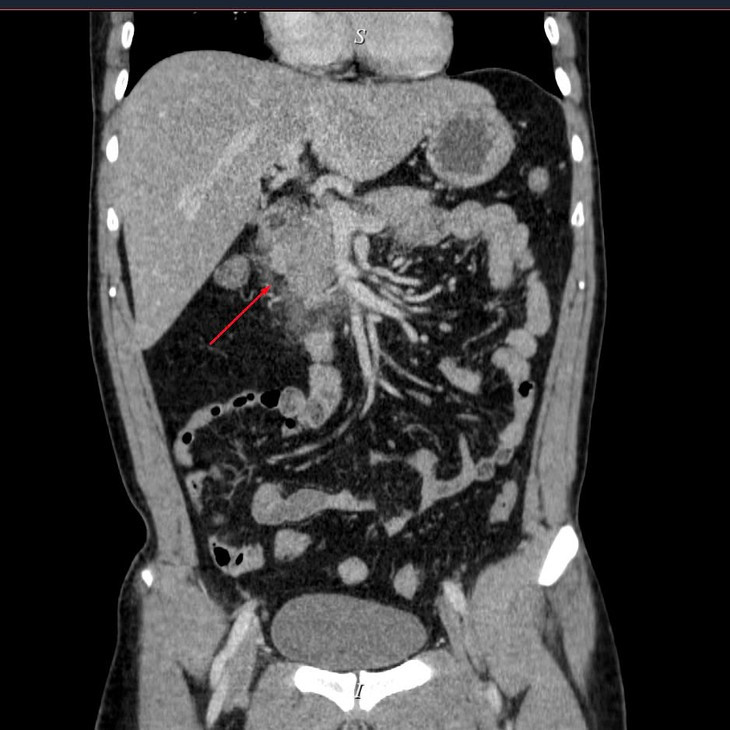

Viêm tụy cấp trên phim chụp - Ảnh BVCC

Kết quả chụp CT Scanner đa dãy ổ bụng có thuốc cho thấy: Hình ảnh viêm tụy cấp Balthazar D, mCTSI 4 điểm, xét nghiệm máu triglycerid >73 mmol/ l, khí máu có tình trạng toan Lactat>2. Nhận thấy đây là tình trạng viêm tụy cấp nặng do tăng triglyceride, các bác sĩ khoa Hồi sức cấp cứu Bệnh viện Đa khoa Hùng Vương đã tiến hành lọc máu hấp phụ cho bệnh nhân với mục tiêu là giảm triglycerid, và giảm phản ứng viêm.